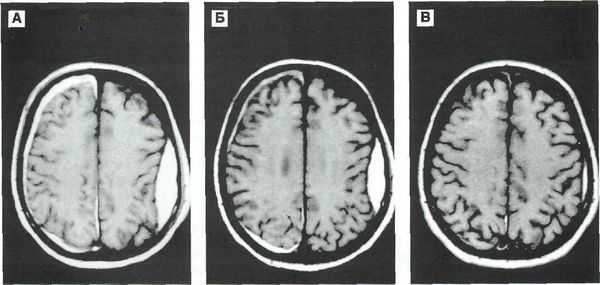

Методом выбора при диагностике ушиба головного мозга является КТ головного мозга. На КТ определяют ограниченную зону пониженной плотности, возможны переломы костей свода черепа, субарахноидальное кровоизлияние. При ушибе мозга средней степени тяжести на КТ или спиральной КТ в большинстве случаев выявляют очаговые изменения (некомпактно расположенные зоны пониженной плотности с небольшими участками повышенной плотности).

При ушибе тяжелой степени на КТ определяются зоны неоднородного повышения плотности (чередование участков повышенной и пониженной плотности). Перифокальный отек головного мозга сильно выражен. Формируется гиподенсивная дорожка в область ближайшего отдела бокового желудочка. Через нее происходит сброс жидкости с продуктами распада крови и мозговой ткани.